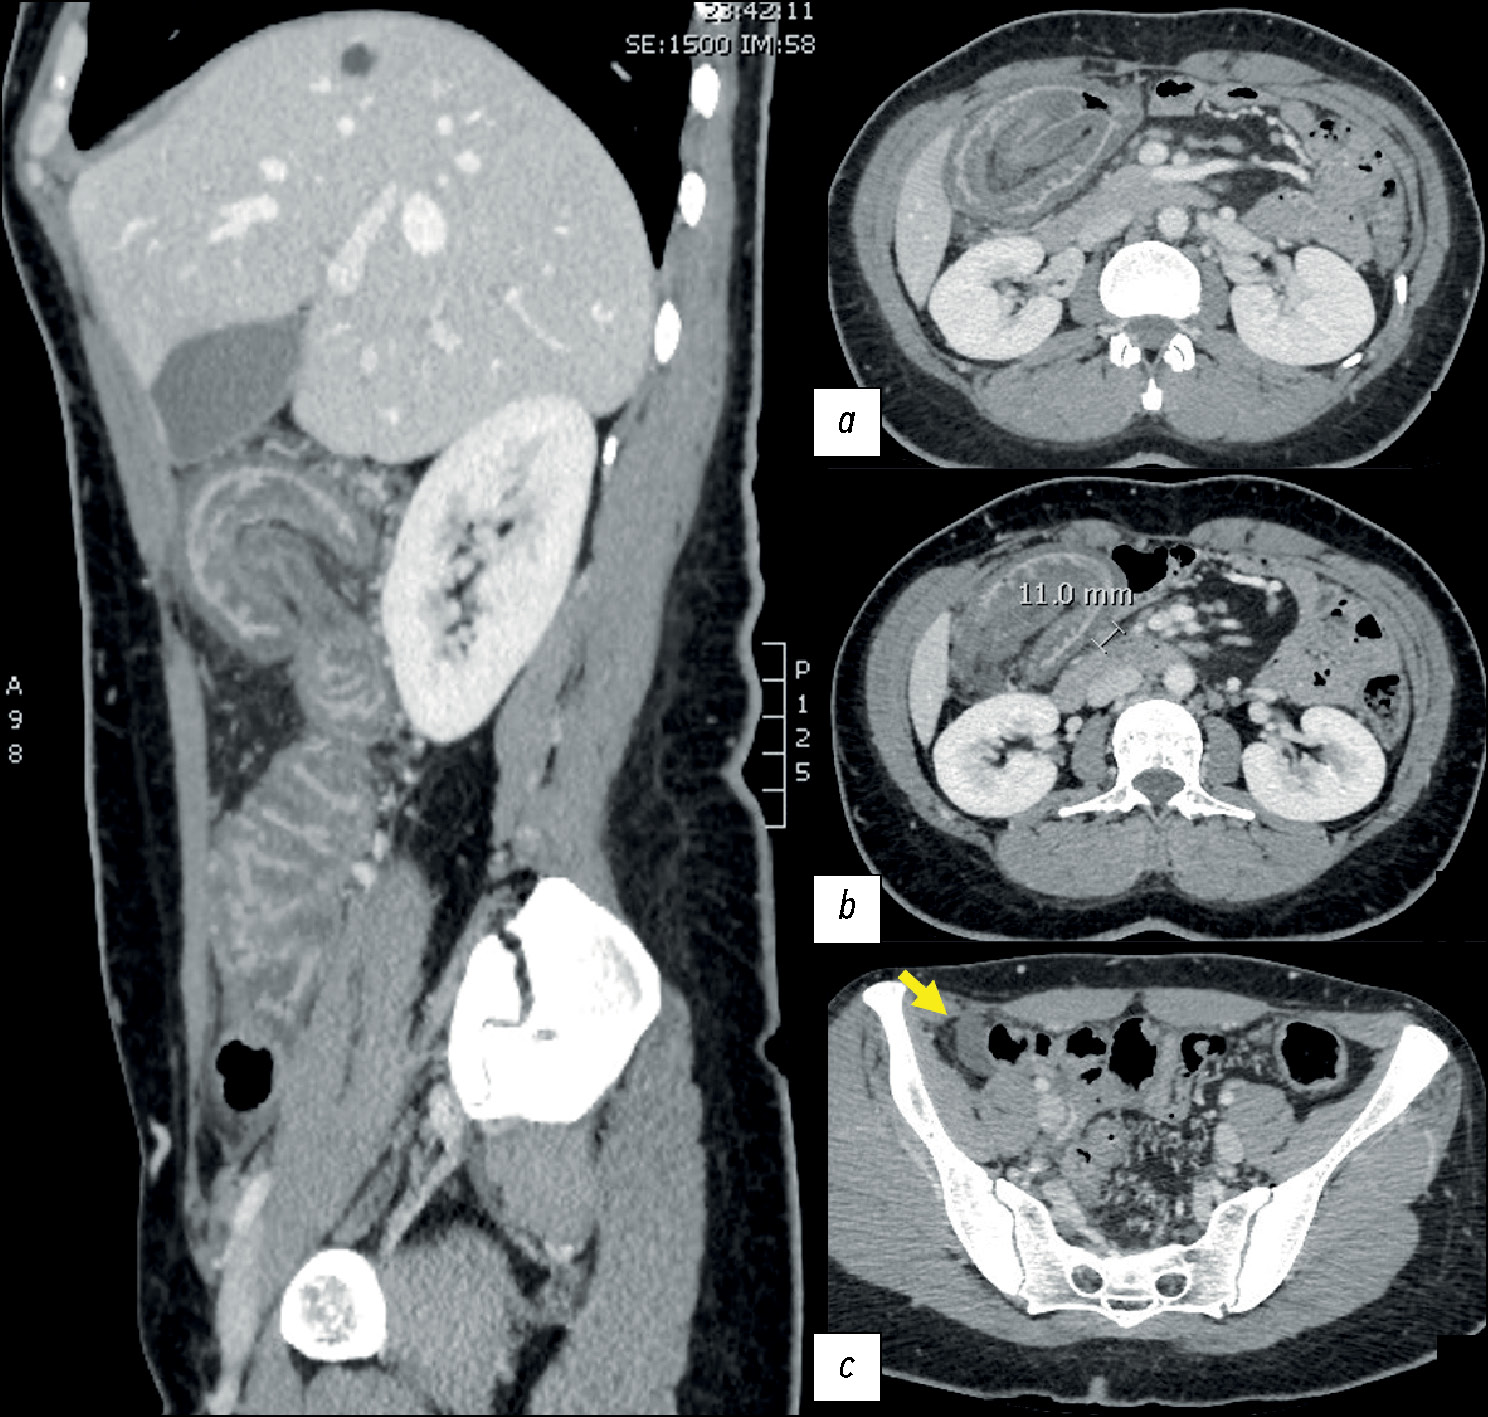

Optimization of left ventricular lead implantation based on combined myocardial perfusion scintigraphy and computed tomography data

Abstract

BACKGROUND: Successful cardiac resynchronization therapy in patients with chronic heart failure critically depends on the selection of the optimal implantation site for the left ventricular lead. A hybrid imaging approach combining cardiac venous computed tomography and myocardial perfusion scintigraphy may assist in identifying the target vein and improve procedural efficacy.

AIM: The work aimed to evaluate the feasibility of a multimodal imaging approach for optimizing left ventricular lead implantation in cardiac resynchronization therapy.

METHODS: It was a prospective, observational, single-center, non-randomized controlled study. Patients with chronic heart failure and indications for cardiac resynchronization therapy in accordance with current guidelines were enrolled. Prior to the procedure, the patients underwent computed tomography of the cardiac veins to visualize venous anatomy and myocardial perfusion scintigraphy to assess the extent of left ventricular perfusion impairment. The optimal site for left ventricular lead placement was identified using a three-dimensional reconstruction of the coronary sinus fused with myocardial perfusion scintigraphy data. To assess the effectiveness of the hybrid approach, a reference group was formed, in which cardiac resynchronization implantation was performed using the standard method, without preprocedural evaluation of coronary venous anatomy or myocardial scarring. Six months after cardiac resynchronization therapy, all patients underwent echocardiography to evaluate treatment effectiveness. Echocardiographic response was defined as a reduction in left ventricular end-systolic volume by ≥15% and/or an increase in ejection fraction by ≥5%.

RESULTS: The imaging group consisted of 40 patients with chronic heart failure, whereas the reference group included 30 patients with the same diagnosis. Six months after cardiac resynchronization therapy, a positive treatment response was observed in 33 patients (82%) in the imaging group, significantly higher than in the reference group (17 patients, 57%), p = 0.031. In the imaging group, the reduction in left ventricular end-systolic volume was statistically significant compared with the reference group and amounted to −52 [−71; −22.5] mL versus −21 [−64; −1] mL, respectively (p = 0.039). The increase in left ventricular ejection fraction was 7.5 [4.5; 15]% in the imaging group and 4.5 [0; 13]% in the reference group, with no statistically significant difference (p = 0.082).

CONCLUSION: The use of cardiovascular imaging methods, including cardiac venous computed tomography and myocardial perfusion scintigraphy, was associated with an increased proportion of responders to cardiac resynchronization therapy.

229-238